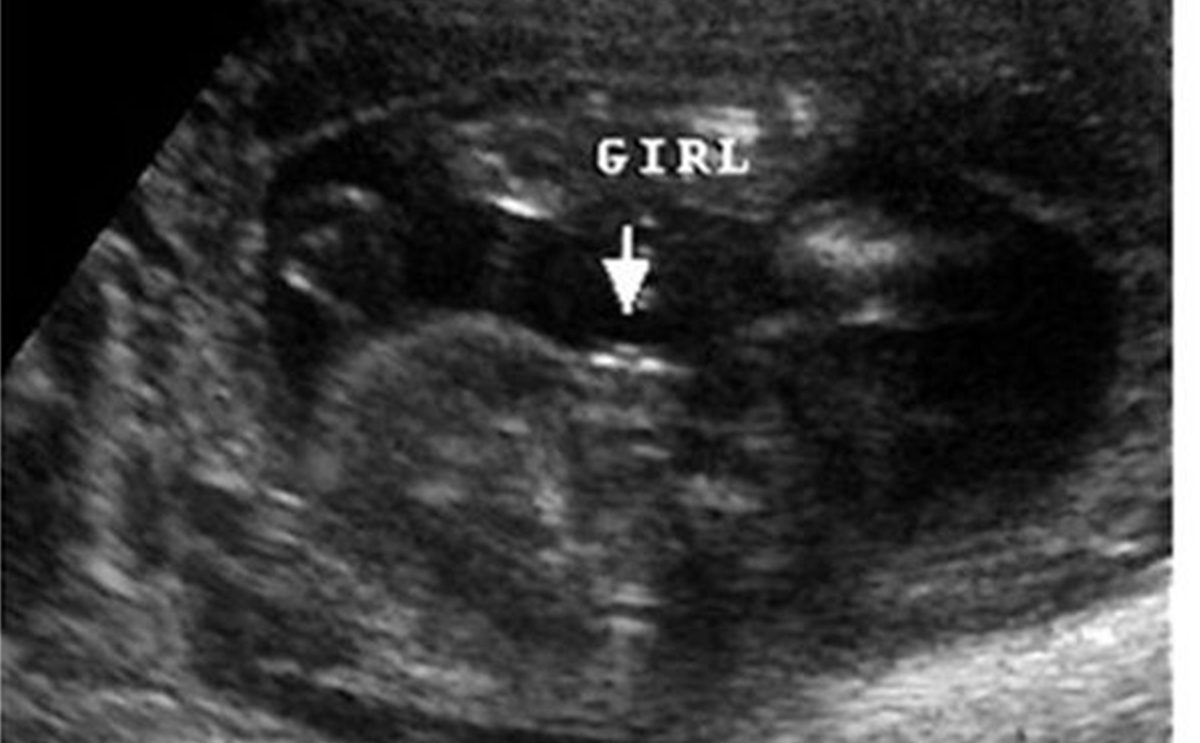

شكل الجنين الانثى بالسونار في الشهر الرابع

أما في حال كان الجنين أنثى، فيكون هناك 3 خطوط بيضاء تمثل شفرات البظر وتدل على ان الجنين بنت.